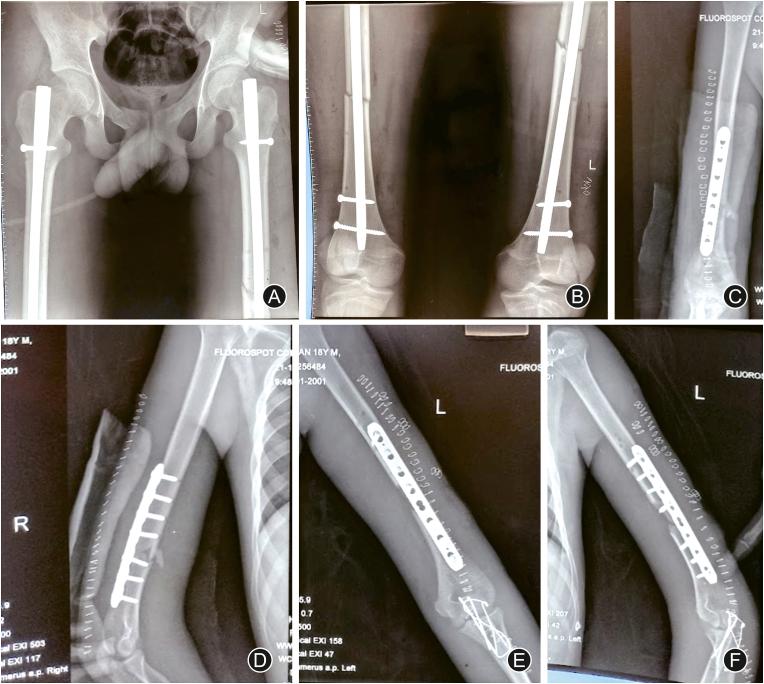

A 19-year-old man had an accidental fall from the 2nd floor and sustained multiple injuries. On radiological evaluation, the patient had symmetrical quadruple limb involvement with bilateral humerus shaft, bilateral olecranon, bilateral femur shaft, and bilateral patella fractures. The patient was actively managed using damage control orthopaedics, and a sequence of skeletal fixation was planned based on the hemodynamic stability and periodical serum lactate assessment. Symmetrical quadruple limb fractures are very rare, which could be associated with higher mortality. A meticulous clinical evaluation, periodical blood parameter assessment and strict adherence to the principles of damage control orthopaedics can be conducive to prevent life-endangering complications.

一名 19 岁男子从二楼意外坠落,多处受伤。影像学评估显示,患者四肢对称性受累,双侧肱骨干、双侧尺骨鹰嘴、双侧股骨干和双侧髌骨骨折。患者采用损伤控制骨科积极治疗,根据血流动力学稳定性和定期血清乳酸评估,计划进行一系列骨骼固定。四肢对称性骨折非常罕见,但可能与更高的死亡率相关。仔细的临床评估、定期的血液参数评估和严格遵循损伤控制骨科的原则有助于预防危及生命的并发症。